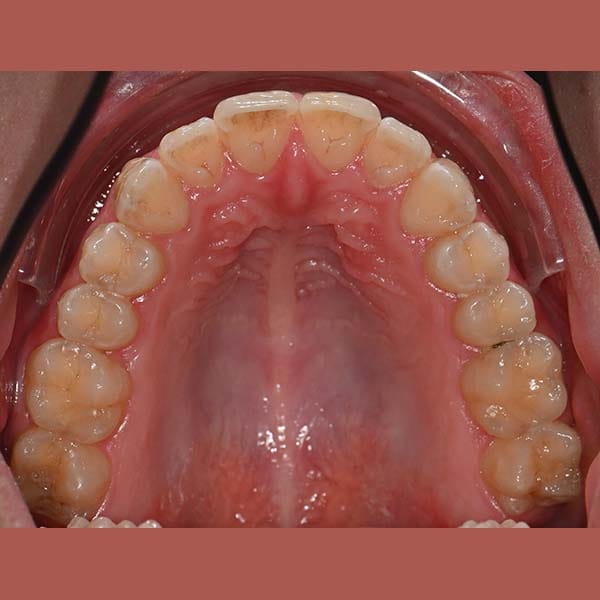

BEFORE

Our young reviewer asked me to treat the simple overlay in her front upper and lower teeth, but she didn’t want anyone to notice her braces. The ideal solution was the invisible braces from Invisalign. After a few months of treatment, all of her teeth were beautifully aligned, and most importantly, no one noticed that she was wearing braces.